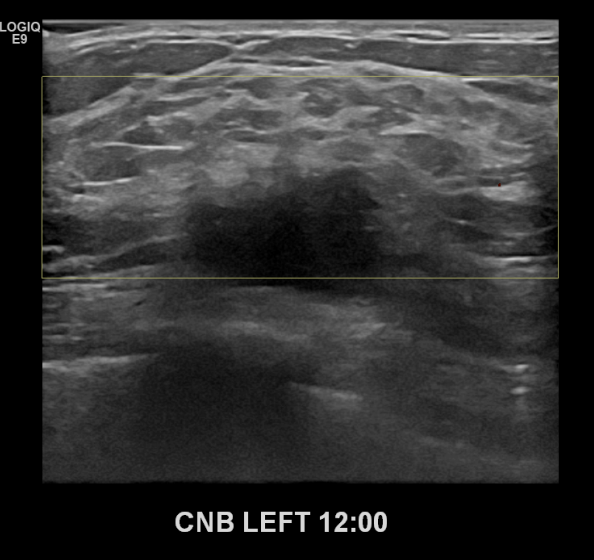

상기환자 만져진멍울있어 내원하신 70대여성분으로 좌측유방

의심스러운 혹 조직검사시행후 유방암 진단되었습니다